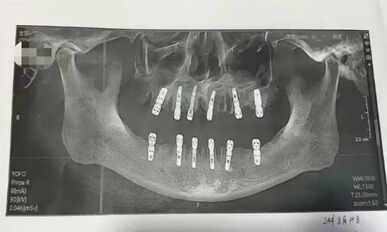

அறுவை சிகிச்சையின்போது அவரின் 23 பற்களும் பிடுங்கப்பட்டு அதே நாளில் 12 புதிய பற்கள் இம்மீடியேட் ரெஸ்டோரேஷன் [Immediate restoration] முறை இம்பிளாட் செய்யப்பட்டுள்ளது.